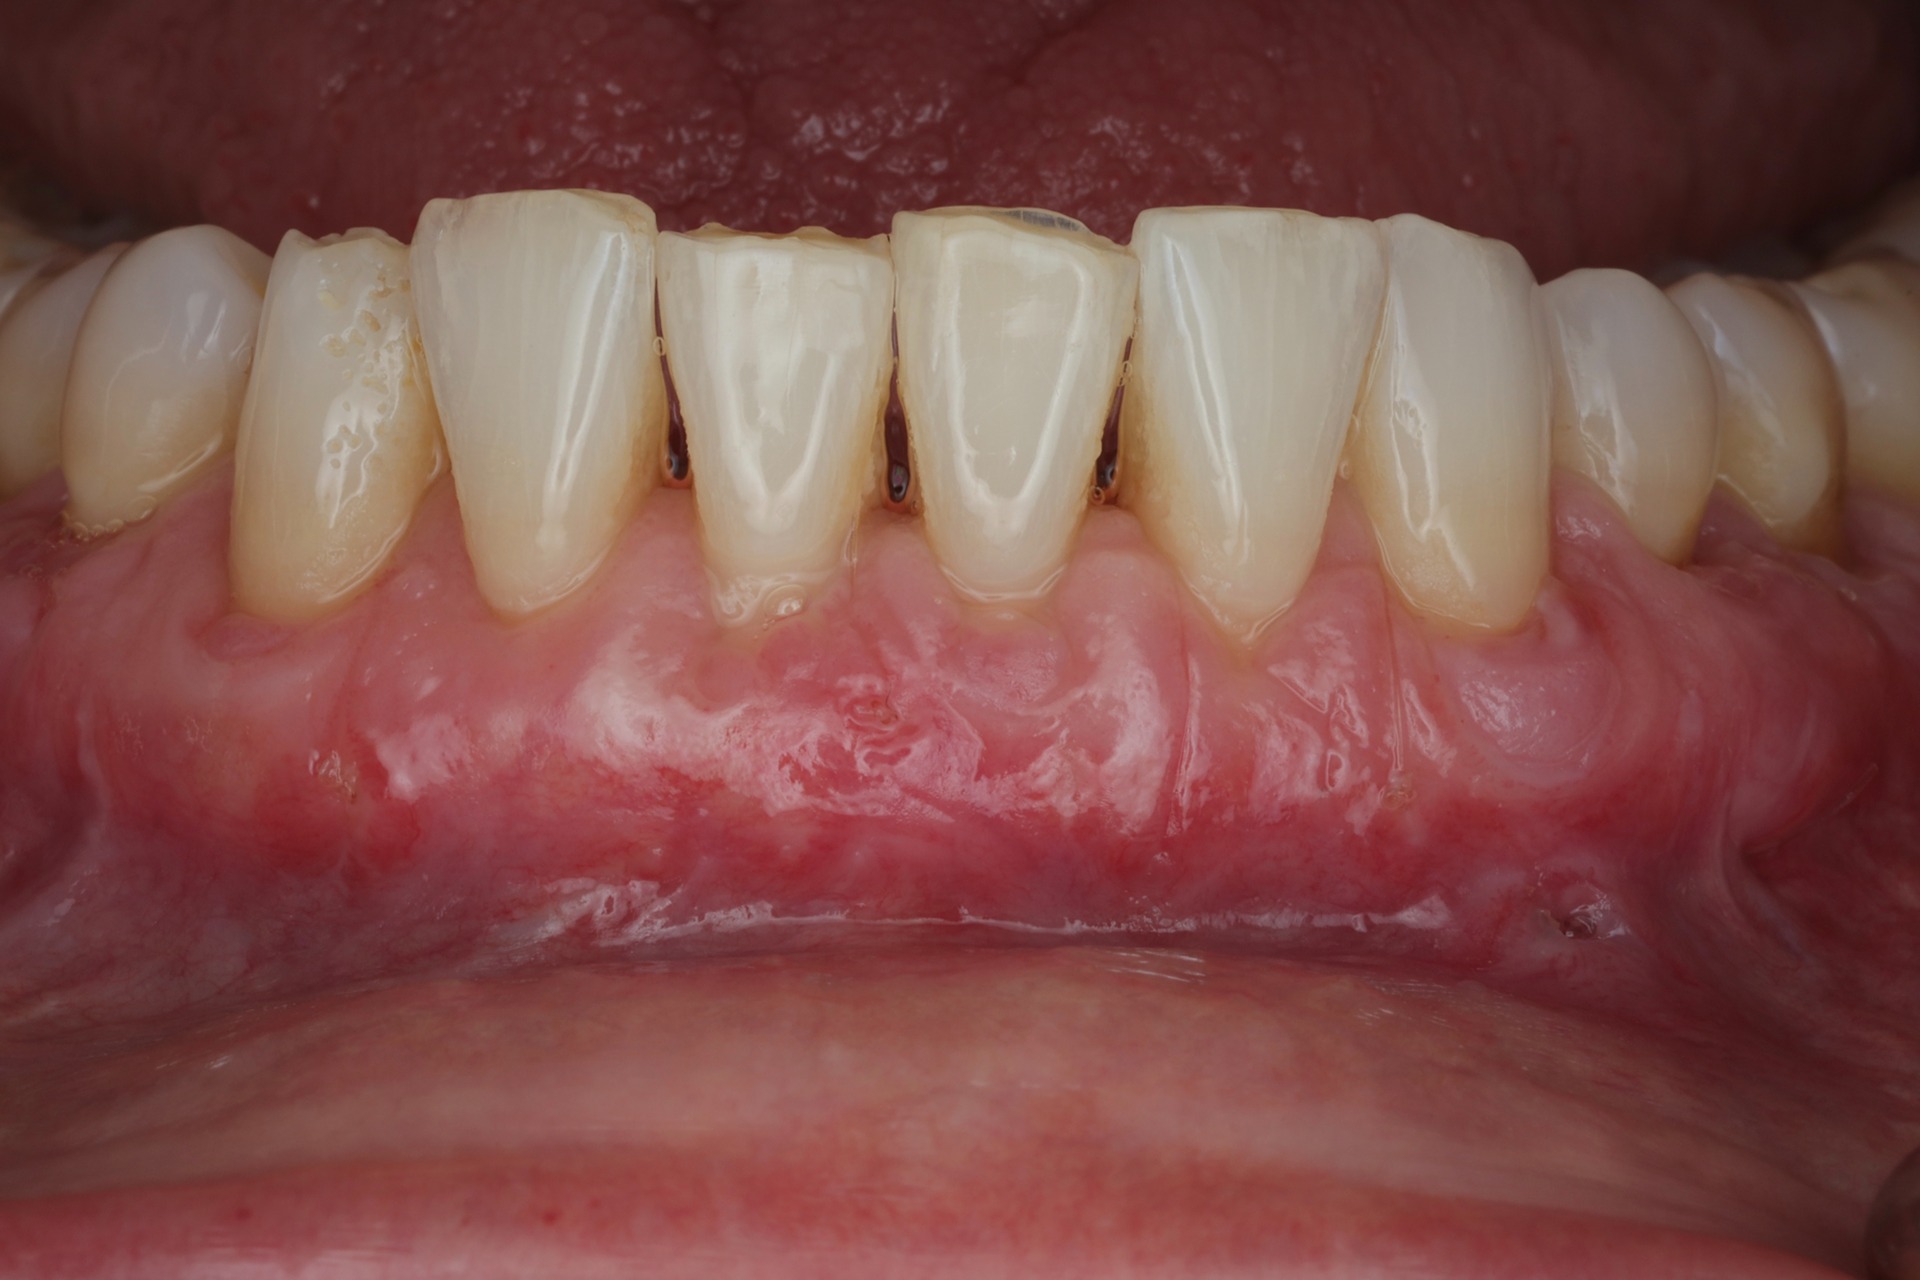

2) Soft tissue flaps – Split vs Full Thickness; Tunneling vs Full Flap

3) Palatal Soft Tissue Harvest – Strip vs Envelop; Keratinization vs Thickening

4) Autogenous Tissue Grafts vs Collagen Biomaterials

The patient treatment by faculty will focus on advanced surgical treatment with implant placement and GBR/soft tissue grafting in the Anterior esthetic zone.